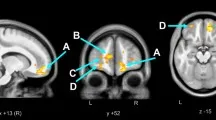

Корреляция показателей ДТВ и мотивации

Были проведены двумерные анализы балла CMS и показателей ДТВ в априорных регионах. Статистически значимые корреляции между CMS и fractional anisotropy (FA — фракционная анизотропия, мера направленной зависимости диффузии воды, отражающая микроструктурную целостность белого вещества), mean diffusivity (MD — средняя диффузия, средняя величина диффузии воды во всех направлениях) и radial diffusivity (RD — радиальная диффузия, диффузия воды перпендикулярно основному направлению волокон) показаны в соответствующей таблице. Отрицательные корреляции наблюдались между CMS и FA в передней ножке внутренней капсулы с обеих сторон и superior corona radiata (справа), и положительные корреляции с MD в поясной извилине (справа) и RD в поясной извилине (с обеих сторон).

Нейровизуализационные аспекты мотивации

Используя ДТВ, мы identified взаимосвязь между баллом мотивации и микроструктурой белого вещества, similar to исследованиям апатии и ВИЧ у взрослых. В частности, показатели ДТВ в передней ножке внутренней капсулы, superior corona radiata и поясной извилине коррелировали с баллом CMS, что suggests целостность белого вещества в этих регионах связана с мотивацией.

Анатомическая значимость фронтостриатальных путей

Передняя ножка внутренней капсулы — это white matter подсоковая структура, расположенная между хвостатым ядром (медиально) и чечевицеобразным ядром (латерально). Она predominantly содержит таламические и стволовые волокна, соединяющие таламус с префронтальной корой (таламокортикальные и кортикоталамические), и лобную долю с ядрами моста (frontopontine), а также поперечные волокна, соединяющие хвостатое ядро и скорлупу. Известно, что передняя ножка внутренней капсулы важна во фронтостриатальных путях, которые часто поражаются ВИЧ.

Направление изменений и интерпретация

Более высокая мотивация была связана с lower FA, мерой целостности белого вещества, в то время как lower мотивация была связана с higher MD и RD в specific фронтостриатальных регионах. Направление эффекта similar to корреляциям между показателями ДТВ и мотивацией, о которых previously сообщалось у подростков, однако оно отличается от некоторых предыдущих исследований у взрослых, живущих с ВИЧ.